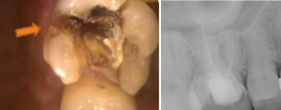

40代女性。左下第二小臼歯の歯根破折。力のかかりやすい臼歯部が失活歯となっており、歯根破折が認められる。この症例の場合、破折を起こした歯に被せ物が装着されていいない事も原因の可能性がある。

40代女性。左下第二小臼歯の歯根破折。力のかかりやすい臼歯部が失活歯となっており、歯根破折が認められる。この症例の場合、破折を起こした歯に被せ物が装着されていいない事も原因の可能性がある。

50代男性。左上第二小臼歯の歯根破折。接合部を切断後メタルコアと装着された被せ物が一緒に外れてきた。

50代男性。左上第二小臼歯の歯根破折。接合部を切断後メタルコアと装着された被せ物が一緒に外れてきた。